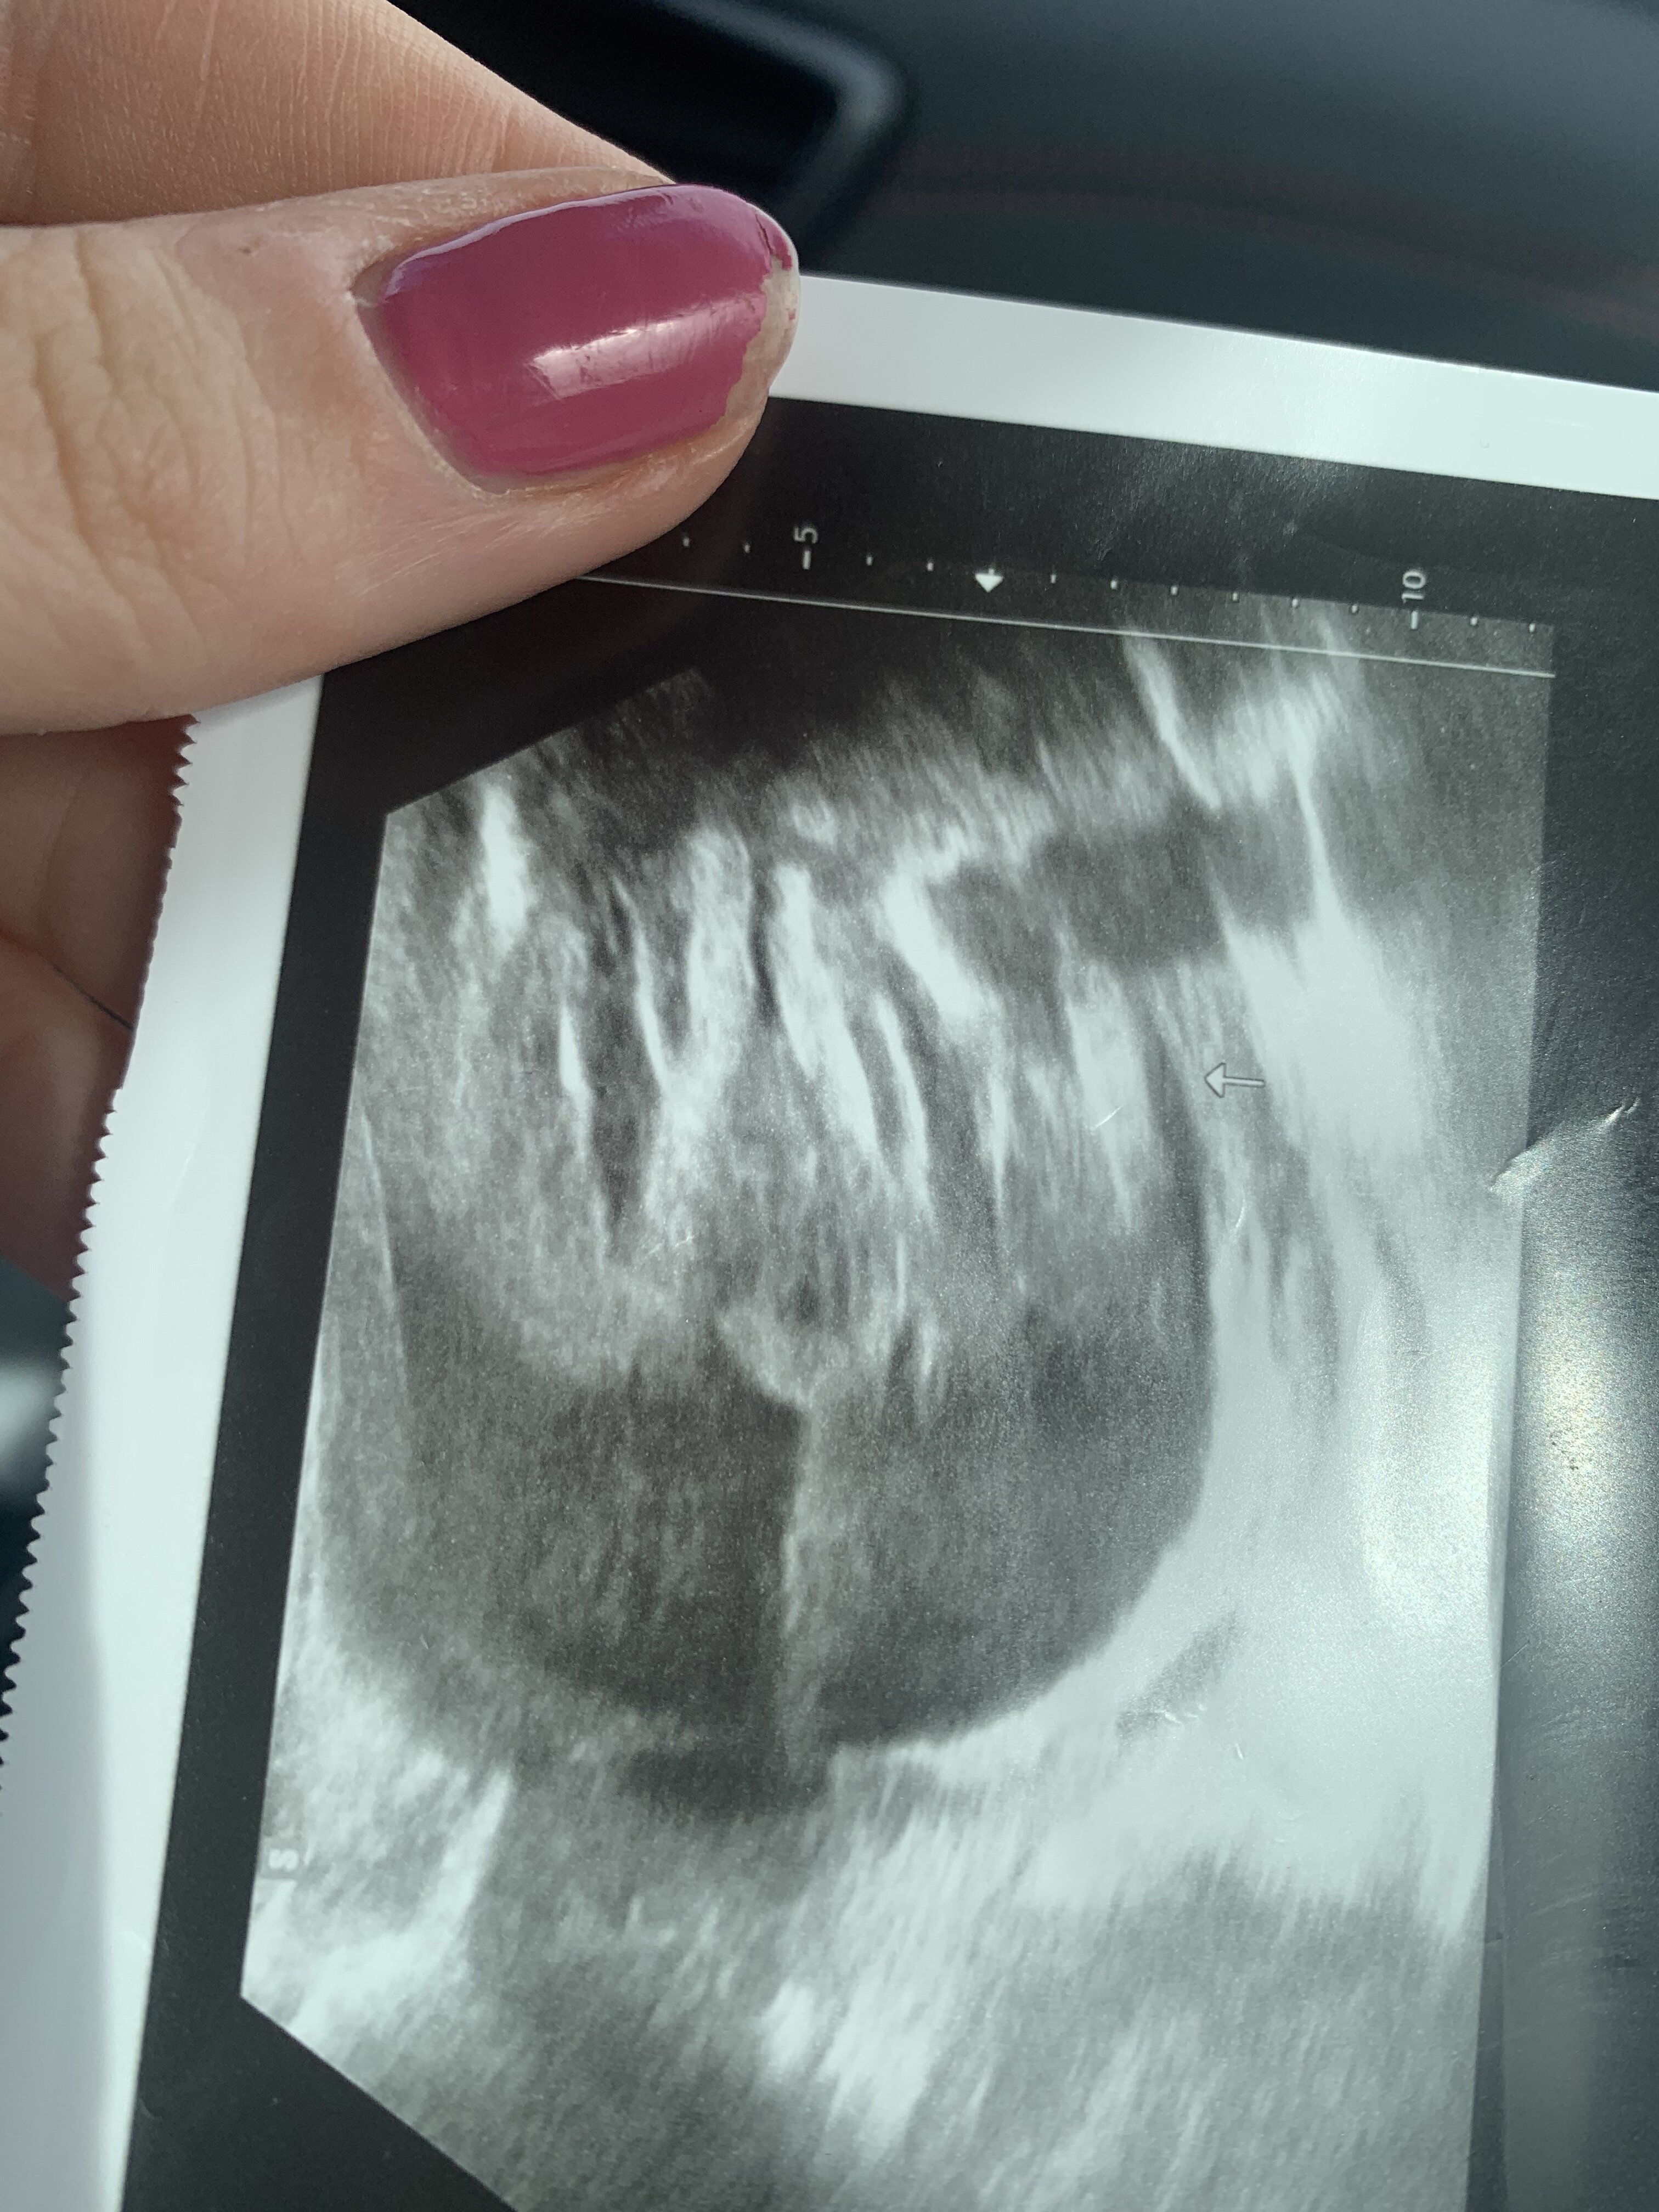

Dziewczynka ?Hej. U mnie zdjęcie z innej perspektywy, z 19 tygodnia +3dni![]()

Byłam pewna, że chłopiec, ale teraz już zgłupiałamDziewczynka ?![]()